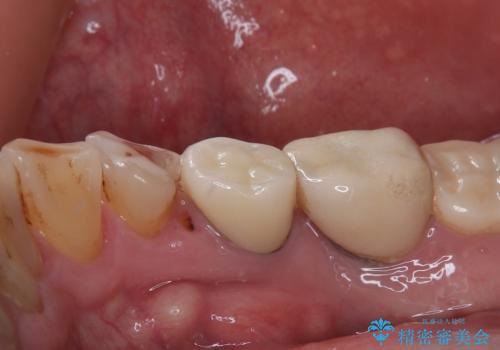

- 食事中に歯が欠けてしまったとのことで来院された患者様です。

以前詰めた材料が外れたか、歯が欠けたのかは分かりませんが、欠損している状態でした。

再度詰め物での処置を行うと引き続き欠けるリスクが高いため、高強度のフルジルコニアクラウンにて補綴治療を行うこととしました。